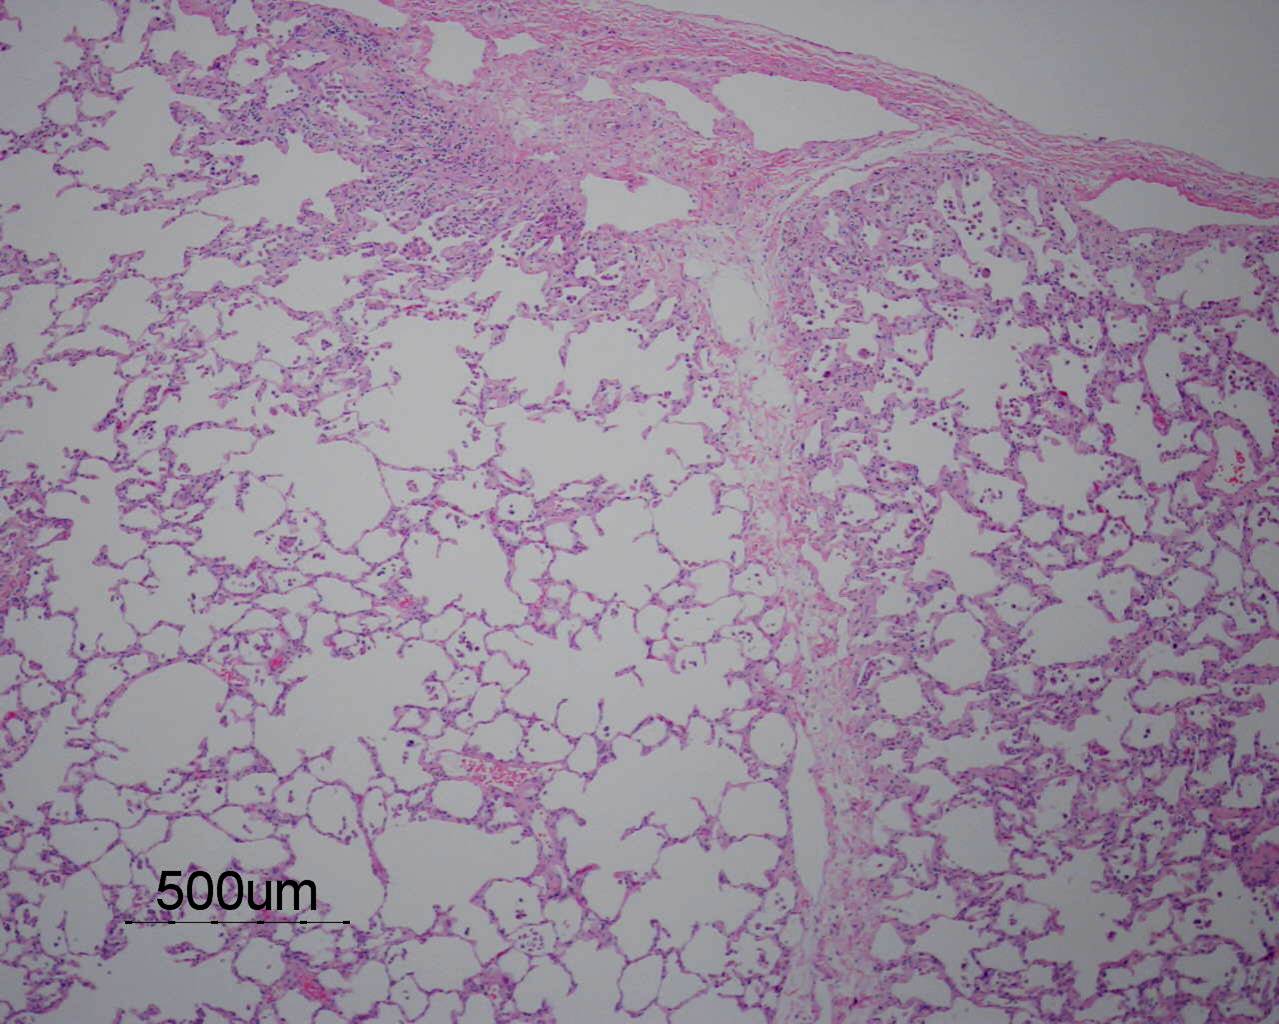

Based on the information found on the CT of the chest, LF underwent an open lung biopsy which showed usual interstitial pneumonitis (UIP) as demonstrated in the pathology below: